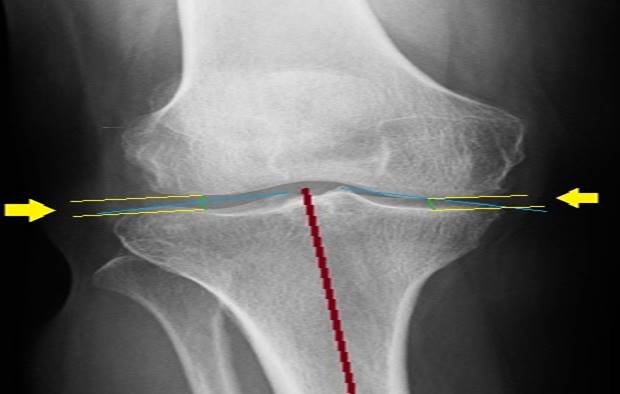

El método del punto medio consiste en trazar una línea por el centro de la tibia, para lo que se determinan dos puntos medios y se unen para conformarla. Luego, se trazan líneas oblicuas desde los bordes más externos mediales y laterales de las espinas tibiales, que terminan en los respectivos cóndilos tibiales. Una vez trazadas estas líneas, se dibujan otras dos en los puntos medios de las oblicuas paralelas a la central de la tibia y allí se determina el espacio articular (Figura 2). 26